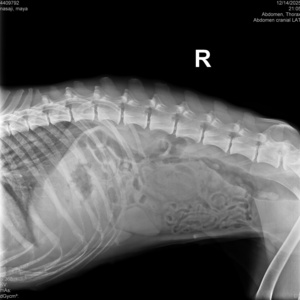

گالری تصاویر

رادیولوژی و سونوگرافی حیوانات در تهران